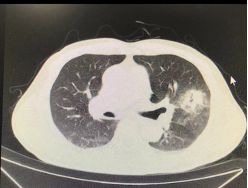

次日早上9点,陈恩国医师开始例行查房工作,走进呼吸与危重医学科15楼西区病房时,只见王大伯手脚灵活地从床边站了起来,声如洪钟地向着陈主任打招呼!眼前的王大伯,身上没有胸外科术后患者常见的胸腔引流管,也没有任何手术刀口,胸壁上也没有针眼,精神抖擞。 术后情况及消融效果 王大伯术后CT提示病灶消融范围理想,消融非常充分,治疗区域完全覆盖原有肿瘤范围,并未见气胸、咯血等并发症。

局部CT术前后对比,原病灶完全被消融范围所覆盖